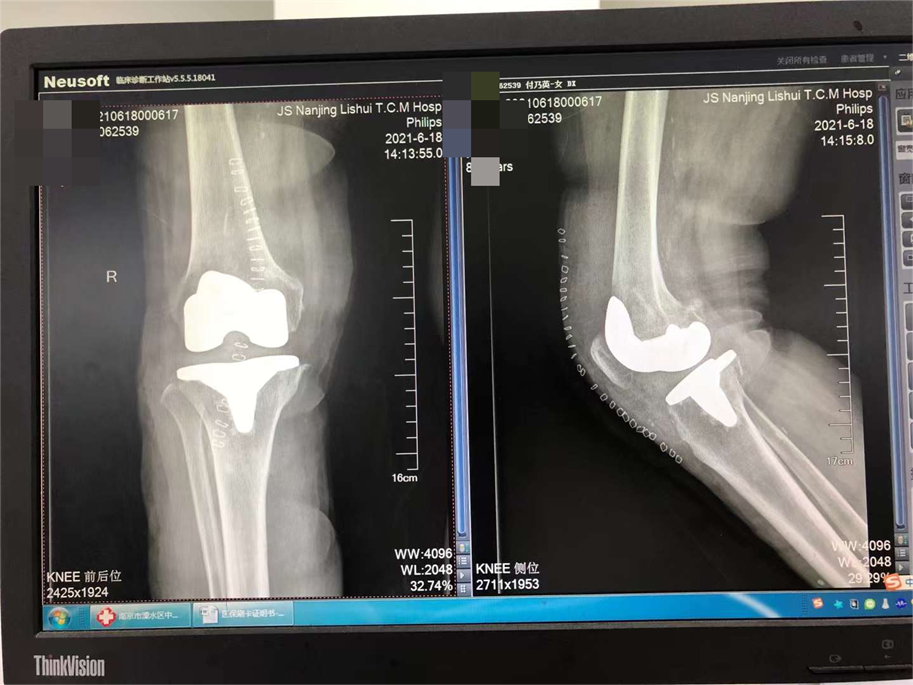

中西医结合治疗骨折是本科的特色;除了运用最先进的手术技术,科室还开展最传统的手法复位小夹板外固定技术,配合自行研发的中药外敷,给患者更好、更多的选择。小夹板固定和骨折微创技术治疗四肢骨折,疗效好,恢复快,效果达到国内先进水平。